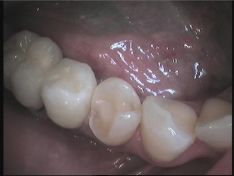

In seconda seduta, quando è ritornato confezionato dal laboratorio l’intarsio, isolo il dente con la diga di gomma e dopo aver adeguatamente condizionato la superficie del dente e dell’intarsio (sabbiatura, silanizzazione, ac. ortofosforico, ecc.) procedo alla cementazione. Il risultato è altamente estetico e, dato il tipo di procedura particolarmente accurata, è molto difficile che si presentino dolori alla pressione o alle escursioni termiche. Questa certezza mi permette di dire alla paziente che, a fronte di un’igiene dentale accettabile, il mio lavoro deve avere una vita di almeno 10 anni e che sotto tale periodo ogni problema relativo all’intarsio deve essere considerato a carico dello studio.